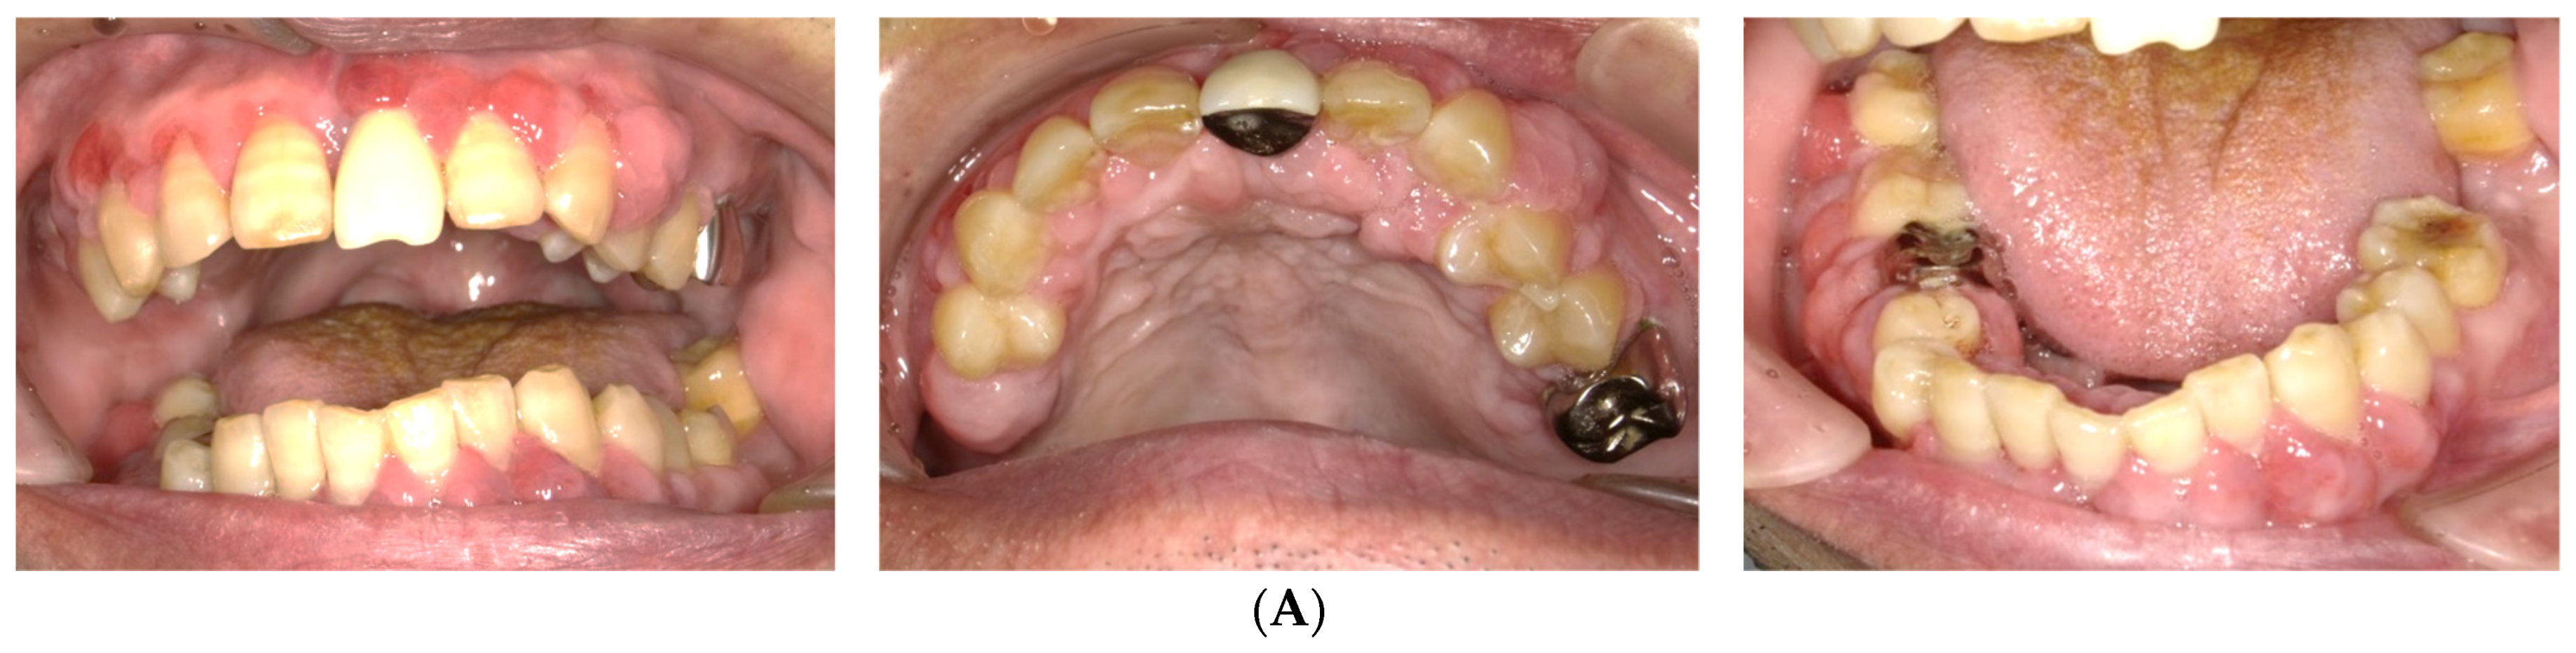

On day 14, the patient’s periodontal condition was seen to have improved following treatment, and the gingival necrosis, redness, and pain resolved (Figure 3). The halitosis had also reduced. After periodontal treatment, six teeth had a poor prognosis (#4, #9, #26, #30, #31, and #32). These teeth had severe mobility and dental caries. We discussed the issues with the patient, and extraction of these problematic teeth was planned considering the patient’s overall well-being and situation, including the general condition, previous and present medical history, medication, paralysis, nursing care system, and the patient’s needs.

Figure 3.

Intraoral photos at 14 days. Acute symptoms, such as gingival redness and bleeding, disappeared.